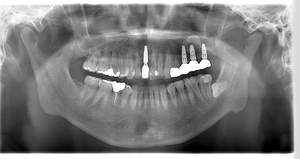

インプラント治療の症例4

レントゲン写真

- Befor

- After

口腔内写真

| 年齢 | 50代・男性 |

| 主訴 | 部位:左下6番7番 主訴:左下奥歯腫れて痛い。 |

| 治療内容 | 左下6番抜歯、左下6番7番骨造成、インプラント埋入 |

| 治療費 | 合計:1,232,000円 ・内訳 診断料:55,000円 サージカルガイド2本:66,000円 GBR:110,000円×2本 埋入料:165,000円×2本 静脈内鎮静麻酔:77,000円 2次OPE:22,000円×2本 仮歯:55,000円×2本 上部構造(フルジルコニア):165,000円×2本 (2023年1月現在) |

| 治療期間 | 約8ヶ月 |

| 治療方針 | 元々支台歯に負荷がかかりやすいとされている延長ブリッジを抜歯し、1本単体でしっかりかめるようにインプラントを2本埋入した。骨吸収も進んでいたため、※GBR法で骨造成を同時に行った。 治療と並行して、全顎的な歯周病治療も行い、今後は歯周病が進行しないよう、こまめにメンテナンスに通っていただく。 |

| 特記事項 | ※1 GBR・・・骨再生誘導法。骨の高さや厚みを人工骨や人工膜などを使用し再生する方法 |

| 担当者所見 | 6番は歯根分割された被せ物が7番の欠損部との延長ブリッジとされており、強い咬合と歯周病も相まって負荷がかかり動揺し、歯として機能しなくなったため、抜歯となった。 |